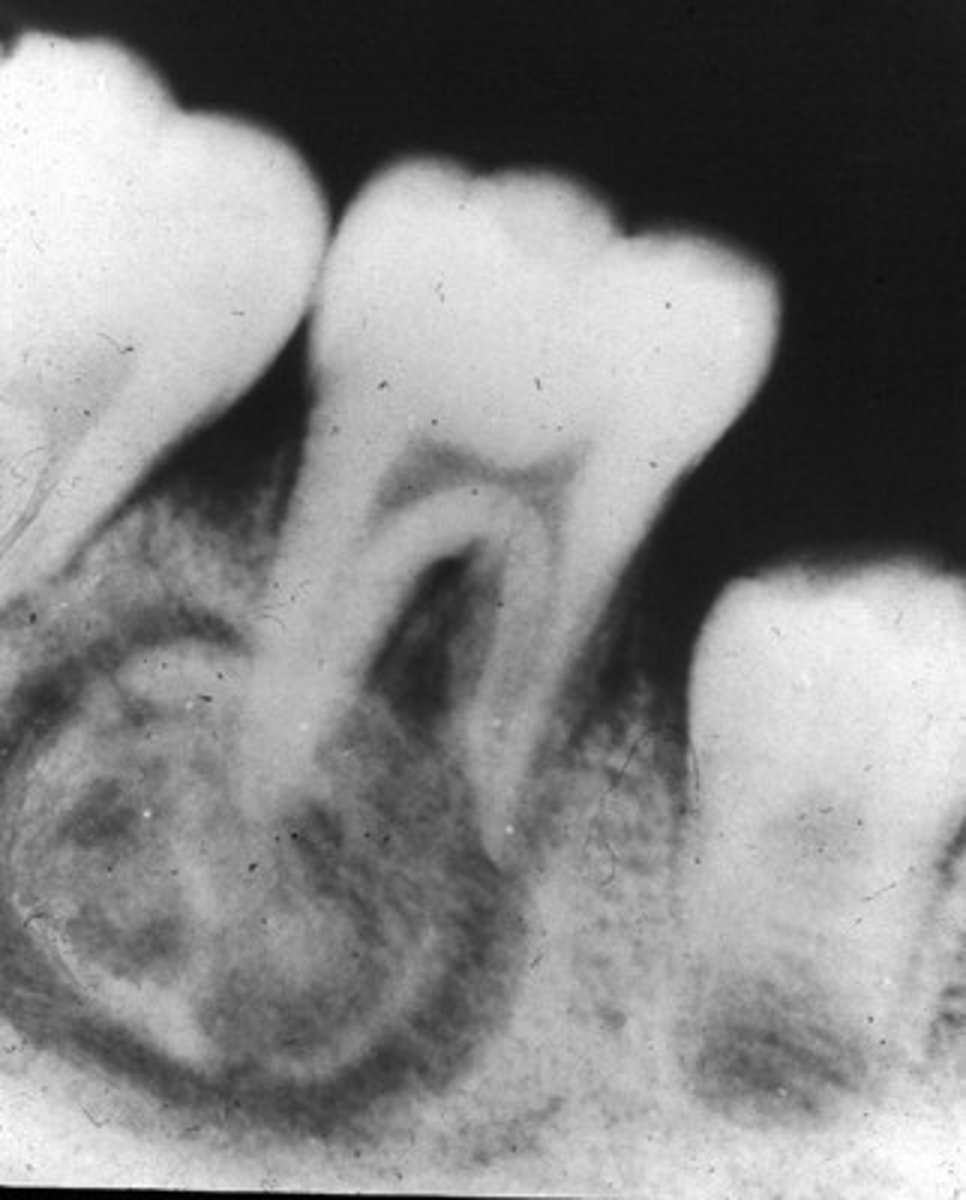

What does a Benign Cementoblastoma appear like on radiograph?

Wheelspoke pattern

What type of teeth are affected by Benign Cementoblastoma?

Vital teeth

What age group and gender are most affected by Benign Cementoblastoma?

Males, any age

What growth is associated with Benign Cementoblastoma?

Bulbous growth at apex

What is a characteristic of Benign Cementoblastoma on the tooth root?

External resorption of root